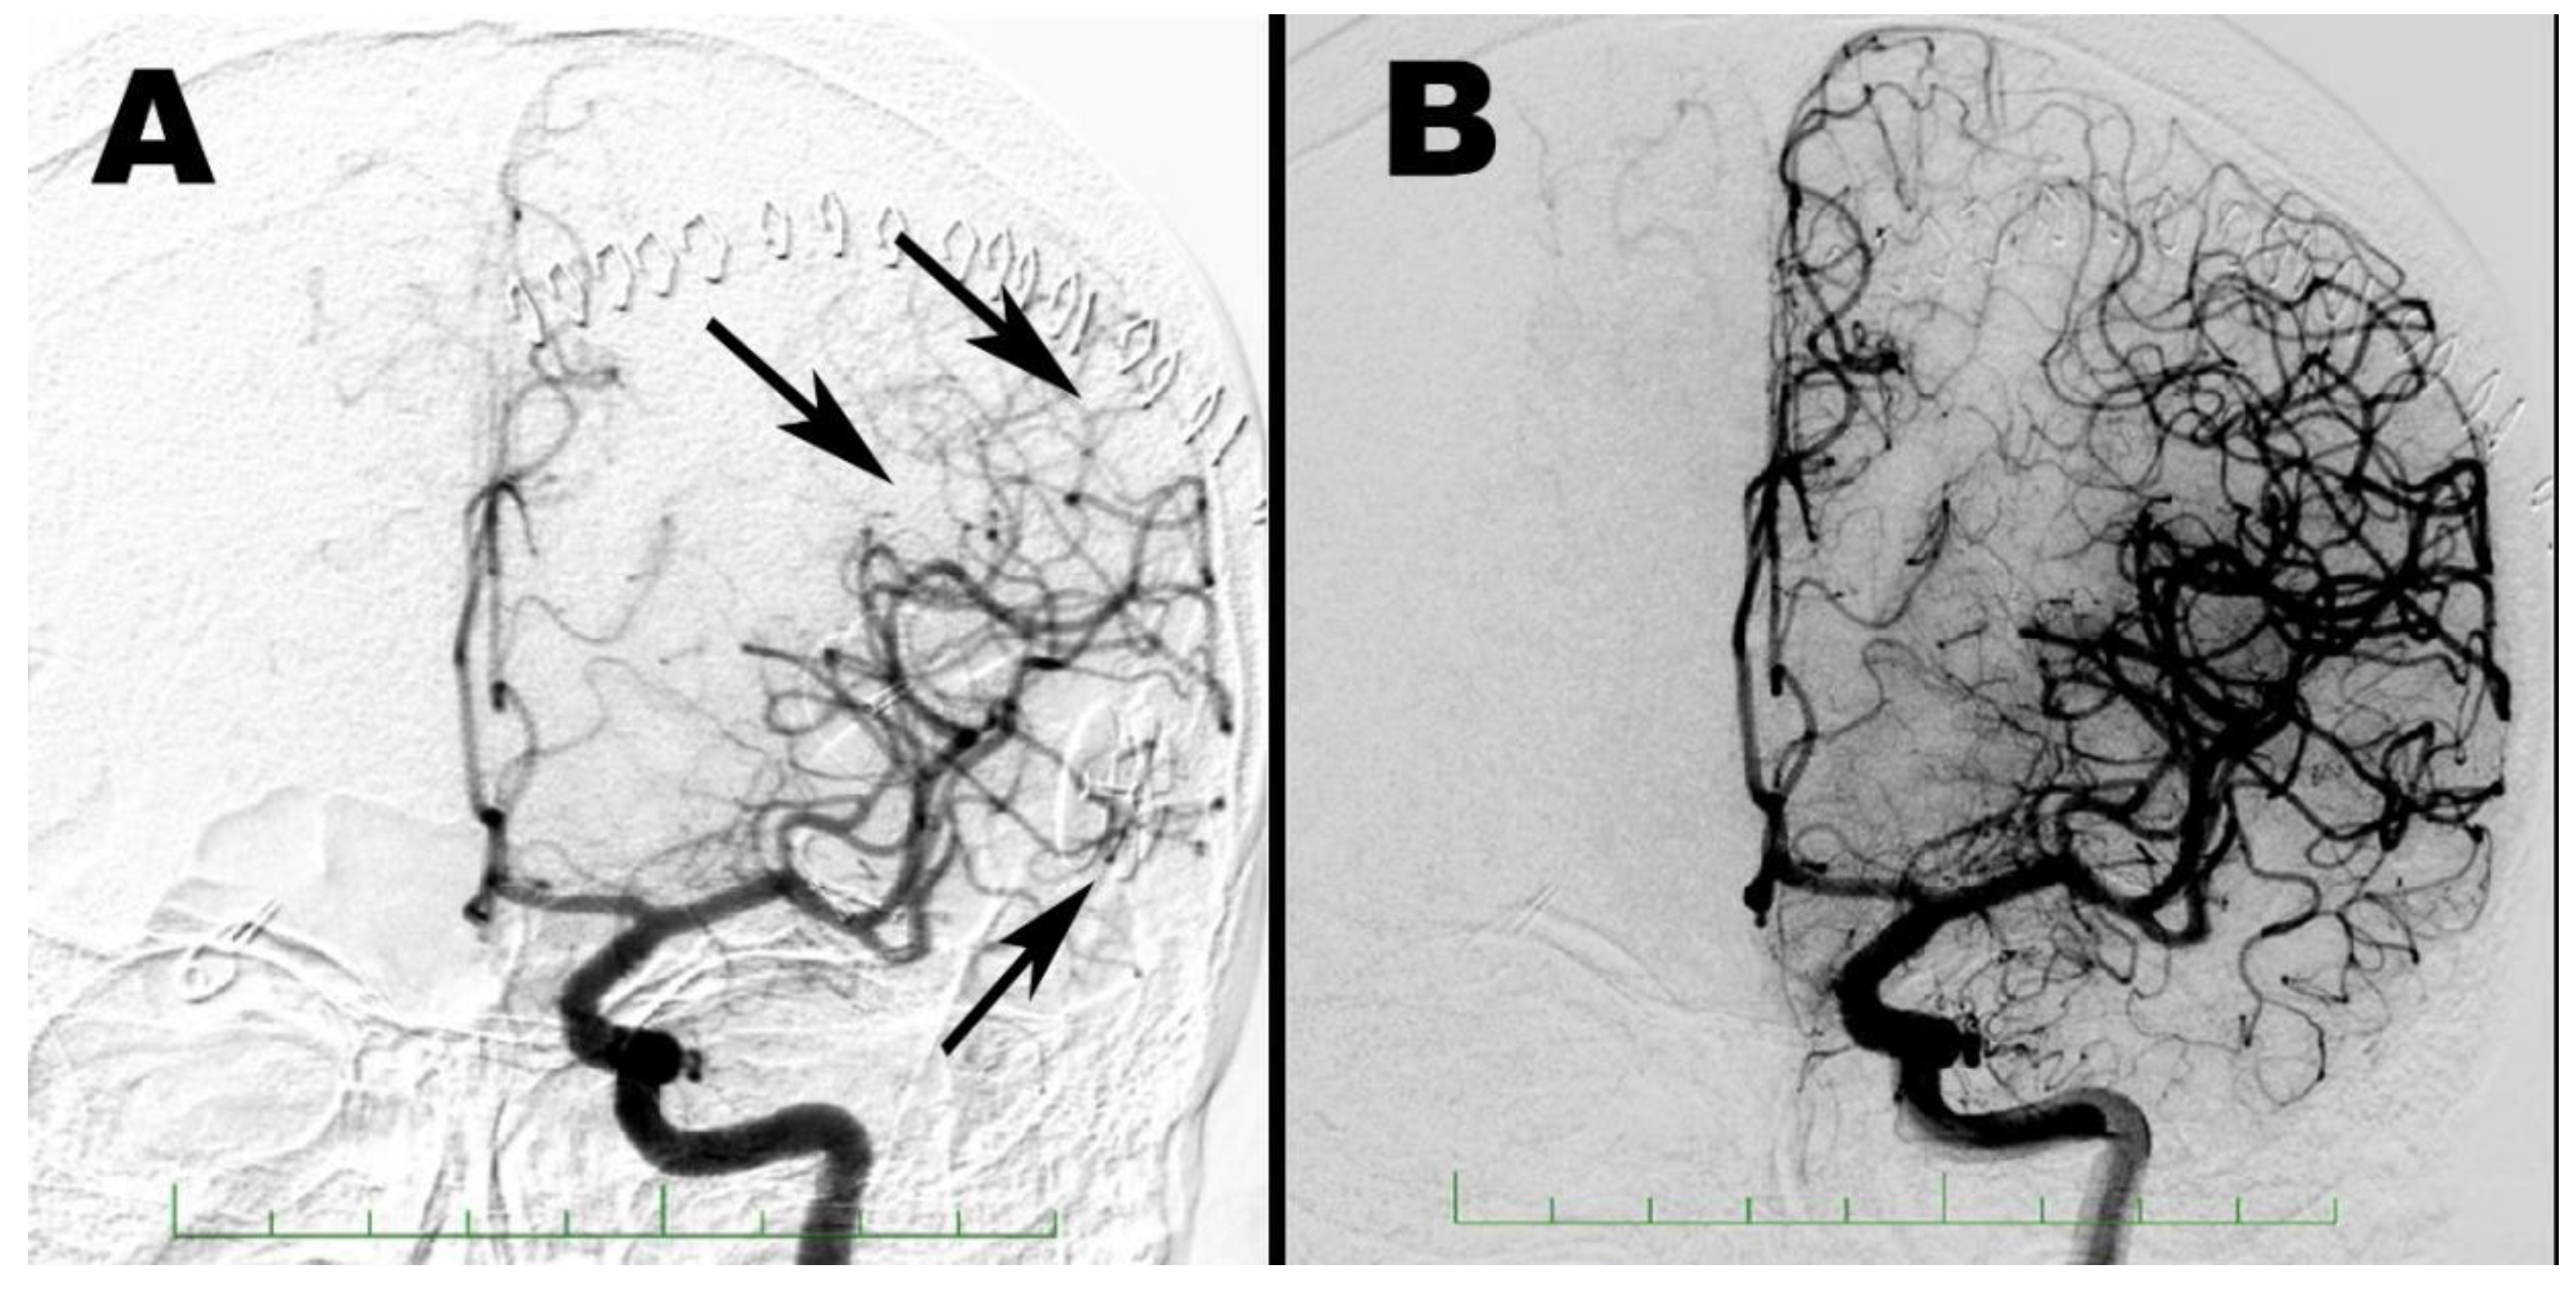

2. Case Report 1

3. Case Report 2